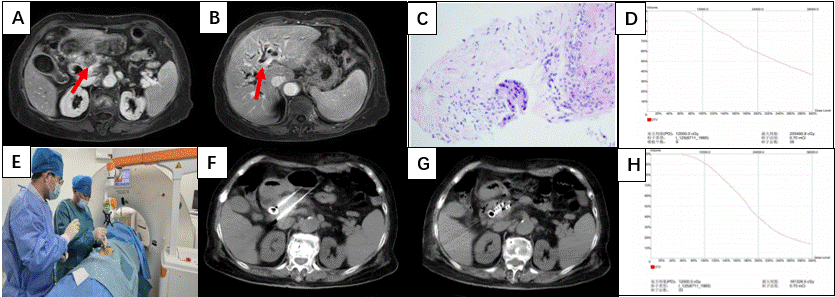

患者因“左上腹胀痛2月”来院,行上腹部强化MR检查,示:胰腺占位,考虑胰腺癌,且合并胆道低位梗阻、胰管扩张(图A、B)。进一步行CT引导下胰腺占位穿刺活检,病理示:胰腺导管腺癌(图C)。完善系统检查后,患者诊断为:胰腺导管腺癌(cT2N0M0IB期),并于2月24日行内镜下胆道支架植入术以解除胆道梗阻,经对症治疗后患者相关指标恢复正常。

后经多学科讨论,结合患者高龄、外科手术风险高的情况及家属意愿,于3月2日在行机器人辅助胰腺癌放射性碘125粒子植入术,由危志刚副主任医师、薛国亮副主任医师及曹丕坤主治医师实施手术操作,手术过程顺利(图E-G)。

此次手术严格按照术前计划执行,精准植入0.7mCi 125I粒子33粒,术后验证参数达标(图D、H);患者术后2天上腹疼痛明显减轻,肝功指标改善,无腹腔出血、感染等并发症。相比传统CT引导介入治疗,机器人辅助创伤更小、安全性更高、粒子排布更均匀、手术时间更短,为高龄无法耐受根治性手术及全身治疗的胰腺癌患者,提供了一种高效、安全的治疗策略。